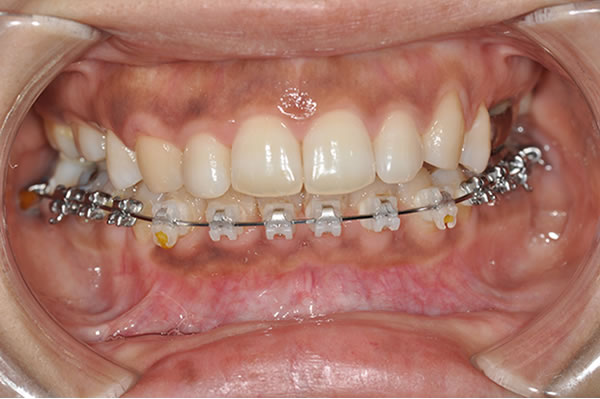

上顎前突症の治療例

上顎前突症(出っ歯)の矯正症例 ケース01

装置 |